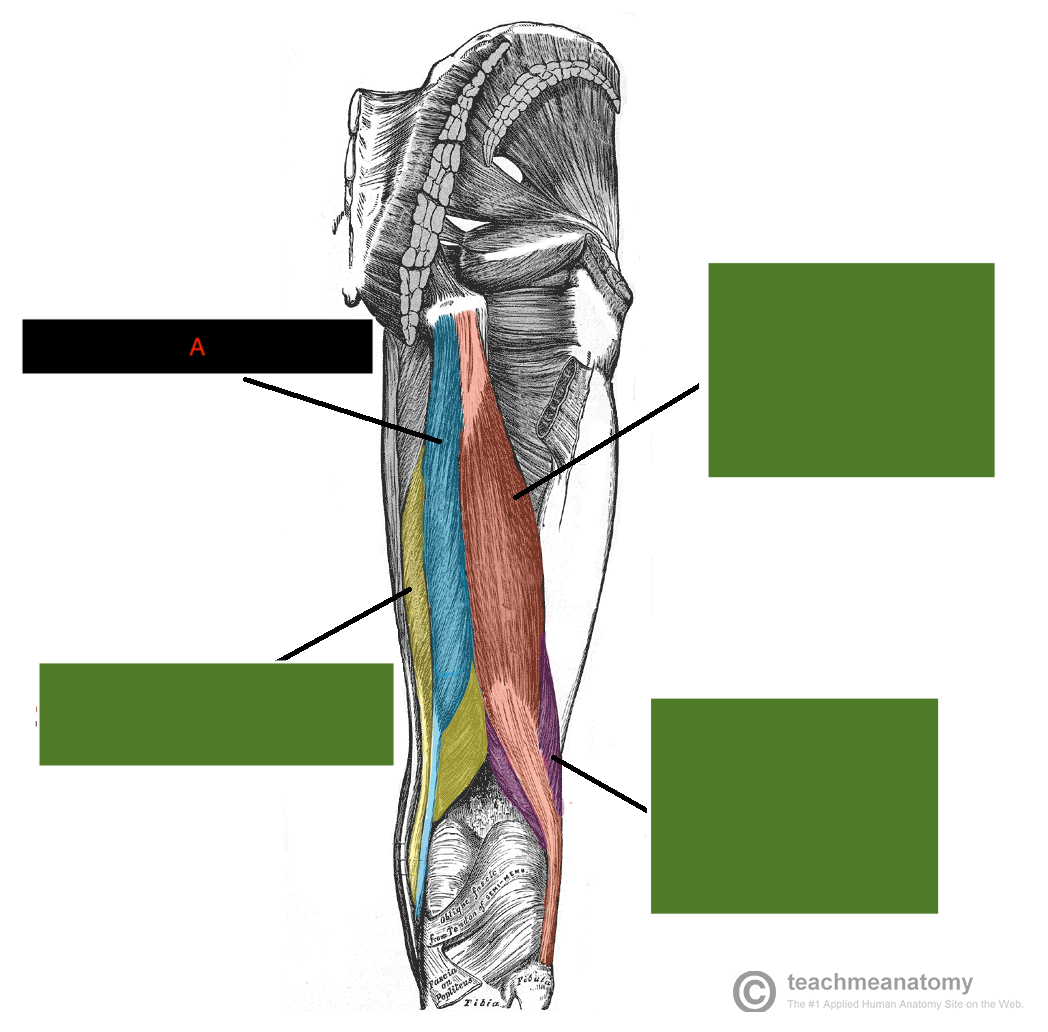

which is muscle A?

semitendinosus muscle (bc superior portion is almost aporneurotic)

which muscle is A&B?

what are origins of A&B?

Bicep femoris

A - long head - comes from common hamstring - ischial tuboristy

B - short head - comes from posterior aspect of femur, laterally